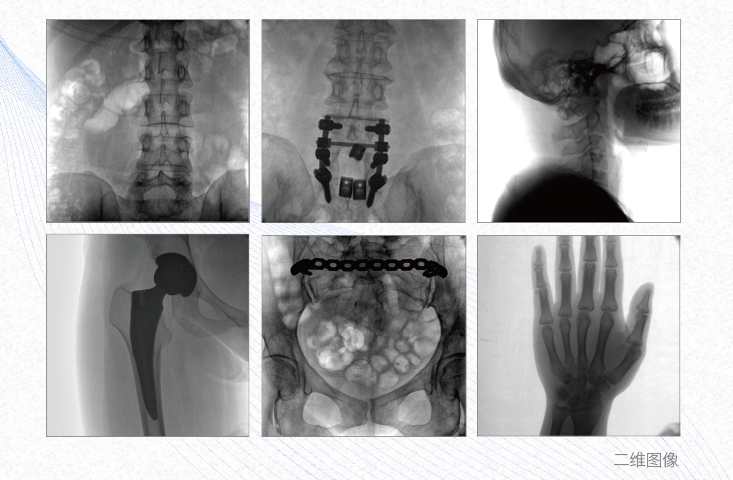

有效重建復(fù)雜的脊柱三維模型,提供準(zhǔn)確的二維、三維圖像,提高螺釘植入的準(zhǔn)確性,縮短手術(shù)時(shí)間,減少并發(fā)癥的概率,降低輻射的攝入。

例如骨盆骨折內(nèi)固定術(shù),可術(shù)中三維重建髖臼關(guān)節(jié)面,準(zhǔn)確定位并植入螺釘,有效縮短螺釘植入的時(shí)間和透視暴露時(shí)間,減少術(shù)中及術(shù)后并發(fā)癥發(fā)生的概率。

主要應(yīng)用于肩關(guān)節(jié)、肘關(guān)節(jié)、髖關(guān)節(jié)、膝關(guān)節(jié)的關(guān)節(jié)置換及解剖復(fù)位的定位。它可以準(zhǔn)確地置入假體,減少輻射時(shí)間,降低輻射劑量。

例如治療先天性脊柱側(cè)后凸畸形,可有效引導(dǎo)術(shù)者植入后路螺釘并切除半錐體,達(dá)到滿意的截骨矯正效果。

術(shù)中三維成像和橫斷面圖像提供多角度的手術(shù)診斷信息,輔助醫(yī)生進(jìn)行術(shù)中評估判斷,諸如骨折復(fù)位情況和內(nèi)植入螺釘?shù)某叽绾臀恢?,輔助手術(shù)更好地完成。

提供更大的術(shù)中三維成像視野,采集更多圖像信息,可一次拍全全段頸椎、全段腰椎、七節(jié)胸椎、雙側(cè)骶髂關(guān)節(jié)、股骨頭及單側(cè)盆骨。